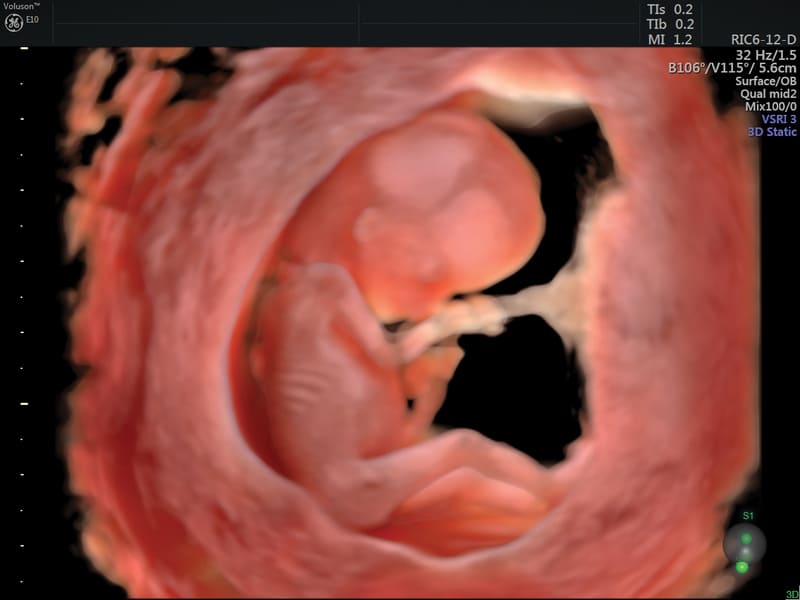

HDlive™: tecnologia di rendering del data set volumetrico che genera immagini incredibilmente realistiche del feto.

HDlive™ Silouette: tecnologia che permette aggiungere ai rendering realistici l’effetto trasparenza di tutti i volumi acquisiti (in 3D e 4D) per una migliore visualizzazione delle strutture e degli organi interni.

HDlive™ Studio+: espande le funzioni di già disponibili in HDlive™ offrendo la gestione di tre sorgenti fotometriche luminose indipendenti con tre diversi tipi di luce (direzionale, puntiforme, spot) e presenta una funzione speciale di rappresentazione per visualizzare il liquido amniotico.

HDlive™ Flow e HDlive™ Flow Silhouette: Applica tutte le caratteristiche presenti in HDlive™ e HDlive™ Silhouette al rendering con campionamento di flusso volumetrico Color Doppler, Power e HDFlow™.